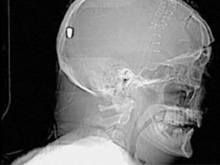

В Британии врачи нашли у пациента пулю в голове13.05.10 13:07 Прочтений новости 880 Общество В Британии у пациента, который поступил в клинику с подозрением на инсульт, врачи обнаружили пулю в голове. Но остается неизвестным, как мужчина получил ранение.Рентгеновские снимки головы показали, что в полости черепа находится инородный предмет. Мужчине сделали томографию головы, и врачи установили, что этим предметом является пуля. Как сообщается, 19 апреля 61-летний Питер Хесфорд упал во время работы у себя в саду. Позже его обнаружила жена, которая вызвала скорую. Мужчина оставался в сознании, но не мог говорить. Медики, прибывшие на место, заподозрили у Питера Хесфорда инсульт и доставили его в Больницу Уитеншо. Эксперты по баллистике, изучив снимки пациента, пришли к выводу, что пуля, застрявшая в затылочной области, могла попасть туда через глаз. Но мужчина не помнит, что именно с ним произошло. Врачи попытались удалить пулю, однако это оказалось невозможным из-за ее положения по отношению к окружающим структурам. Пациент остается в больнице, а его состояние расценивается как стабильное. Комментарии (всего 0)